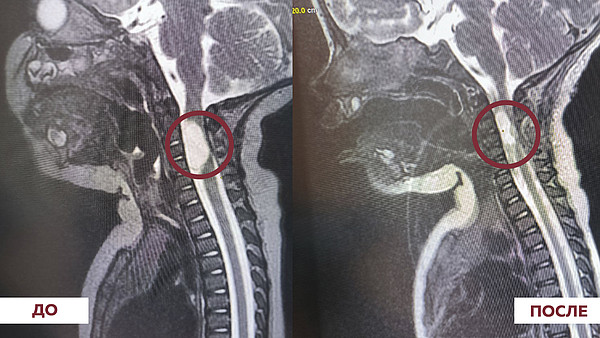

Девочка прошла несколько различных обследований. Ей диагностировали редкую патологию - врожденную арахноидальную кисту шейного отдела позвоночника. Врачи приступили к проведению операции: была вскрыта и дренирована полость кисты. Поскольку она находилась рядом со спинным мозгом, было важно не повредить окружающие структуры - это могло послужить образованию новых осложнений в будущем.

В результате хирургического вмешательства у маленькой пациентки полностью восстановились движения в нижних конечностях и частично в руках. Впереди ее ждут несколько курсов реабилитации.